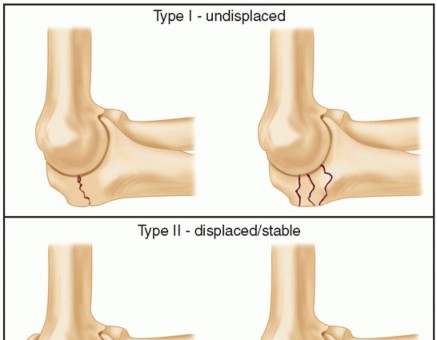

DEFINITION Fracture of the olecranon process is common, usually displaced, and nearly always treated operativ…